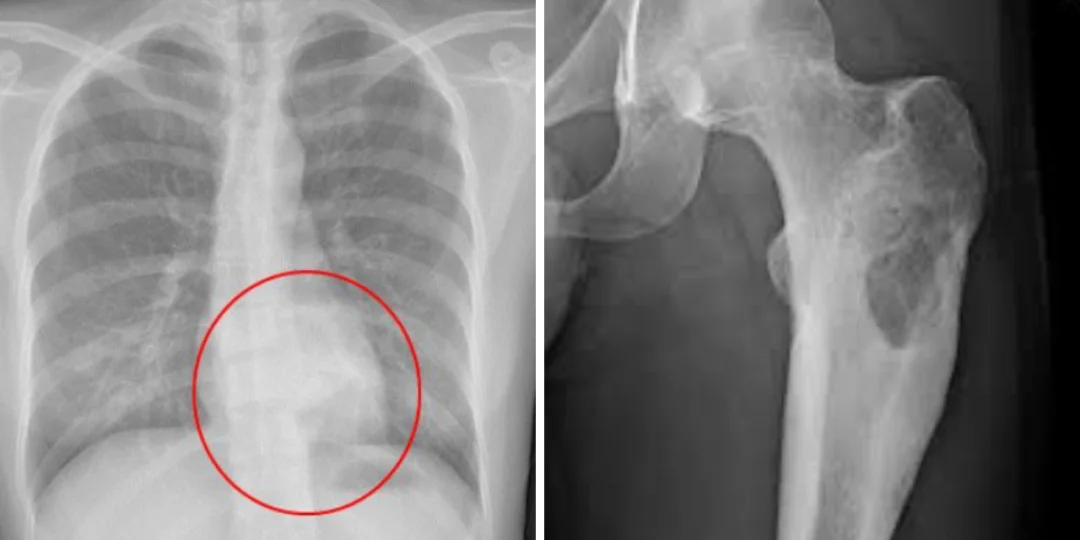

Imagen ilustrativa de osteoblastomas detectados.

Imagen ilustrativa de osteoblastomas detectados. -

"Por lo general, este tipo de tumores —que es un tumor específicamente del hueso y muy raro— es mucho más frecuente en pacientes jóvenes, entre 10 y 25 años. Dentro de los tumores óseos, los osteoblastomas representan apenas el 1%", explicó el especialista.

Según Niewiadomski, los primeros síntomas suelen ser el dolor óseo persistente, inflamación y, en algunos casos, fracturas. Ante estos indicios, es clave avanzar con estudios de diagnóstico: "Empieza con una radiografía, se ve algo dudoso, se pide una tomografía o una resonancia magnética y eventualmente se hace una biopsia para determinar de qué se trata".

De acuerdo con la Biblioteca Nacional de Medicina de Estados Unidos, el osteoblastoma es un tumor benigno que forma hueso y suele aparecer en la columna vertebral y el sacro, aunque también puede manifestarse en otras áreas como la mandíbula o los huesos largos.